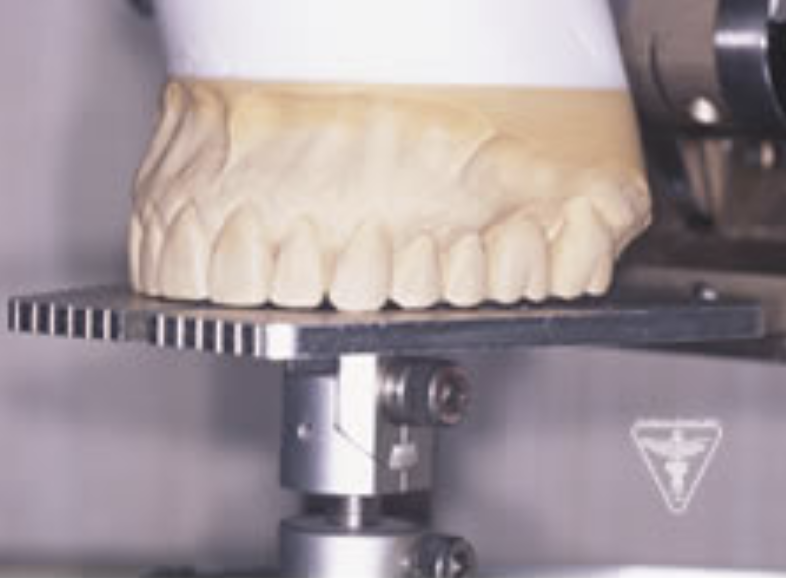

治療前

下の奥歯が左右なくなっており、かみ合わせが深くなっています。

顎のずれは認めませんが、歯肉が厚く中に炎症を取りこみやすいタイプの歯肉です。

左の顎の骨が大きく溶けてなくなっております。